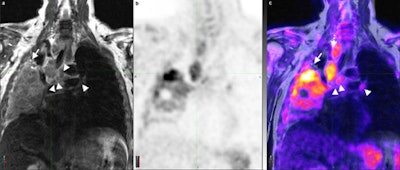

FDG-PET/MRI shows similar performance to FDG-PET/CT for lymph node staging in lung cancer, with "substantial" reader agreement in determining tumor staging, according to a study published online on June 14 in European Radiology.

Using a three-segment model for attenuation correction, PET/MRI for lymph node staging in lung cancer also showed a "strong parallel" to PET/CT relative to maximum standardized uptake values (SUVmax) and diagnostic performance. Lead study author is Dr. Andres Kohan from the department of radiology at University Hospitals Case Medical Center at Case Western Reserve University in Cleveland, Ohio, U.S.

PET with MRI-based attenuation correction for non-small cell lung cancer lymph node staging has a "very strong quantitative correlation to PET/CT, while it may be of a similar qualitative value," Kohan and colleagues concluded.

The potential advantage of using PET/MRI instead of PET/CT for lung cancer is not yet clear, but there may be some cases in which PET/MRI "may be superior, such as lymph node assessment," the researchers noted. "The current experience with PET/MRI in lung cancer is limited."